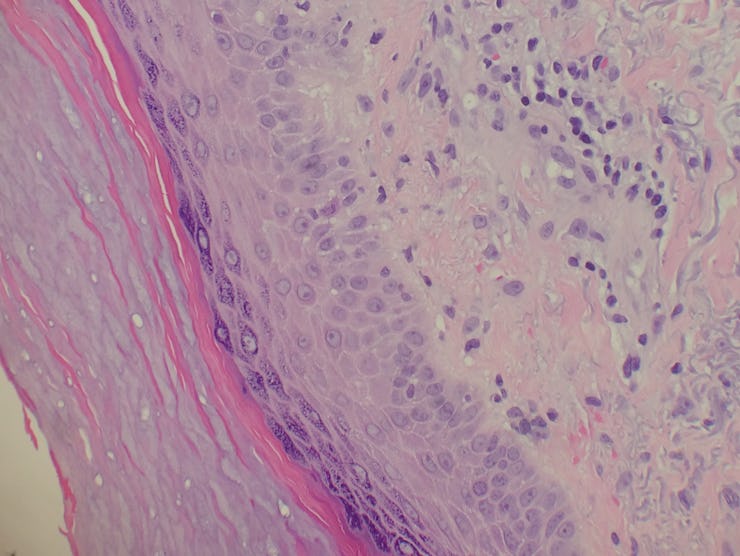

This figure from the study shows the interstitium, fluid filled spaces supported by collagen fiber bundles.

Collagen fibers support the fluid-filled channels that make up the interstitium.

Though some doctors had recently noticed the reticular (that is, net-like) pattern of the interstitium, no one had successfully found a way to sample it. To get past this obstacle, the researchers devised a way to examine bile duct tissue samples obtained during surgeries without losing the structure of the fluid-filled channels. Removing the tissue, they rapidly froze it to retain the reticular structure of collagen fibers and fluid-filled chambers, which are described in the paper.

Abstract: Confocal laser endomicroscopy (pCLE) provides real-time histologic imaging of human tissues at a depth of 60–70 μm during endoscopy. pCLE of the extrahepatic bile duct after fluorescein injection demonstrated a reticular pattern within fluorescein-filled sinuses that had no known anatomical correlate. Freezing biopsy tissue before fixation preserved the anatomy of this structure, demonstrating that it is part of the submucosa and a previously unappreciated fluid-filled interstitial space, draining to lymph nodes and supported by a complex network of thick collagen bundles. These bundles are intermittently lined on one side by fibroblast-like cells that stain with endothelial markers and vimentin, although there is a highly unusual and extensive unlined interface between the matrix proteins of the bundles and the surrounding fluid. We observed similar structures in numerous tissues that are subject to intermittent or rhythmic compression, including the submucosae of the entire gastrointestinal tract and urinary bladder, the dermis, the peri-bronchial and peri-arterial soft tissues, and fascia. These anatomic structures may be important in cancer metastasis, edema, fibrosis, and mechanical functioning of many or all tissues and organs. In sum, we describe the anatomy and histology of a previously unrecognized, though widespread, macroscopic, fluid-filled space within and between tissues, a novel expansion and specification of the concept of the human interstitium.